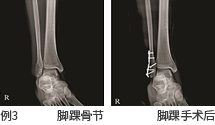

- 检查的目的 : 观察人体解剖学构造,观察骨骼上是否有骨节, 确认软组织是否存在异常,观察患病部位的进程。

- 检查部位 : 头颈部, 胸部, 腹部, 骨骼系统, 小儿摄影等全身摄影